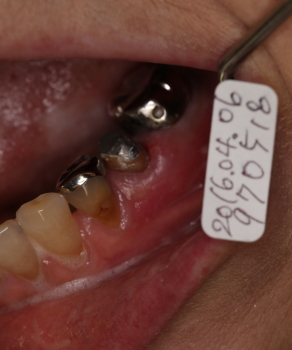

歯槽膿漏による歯ぐきの痛みと骨欠損のケース

2016年04月06日

35番遠心より排膿

同部のX-ray